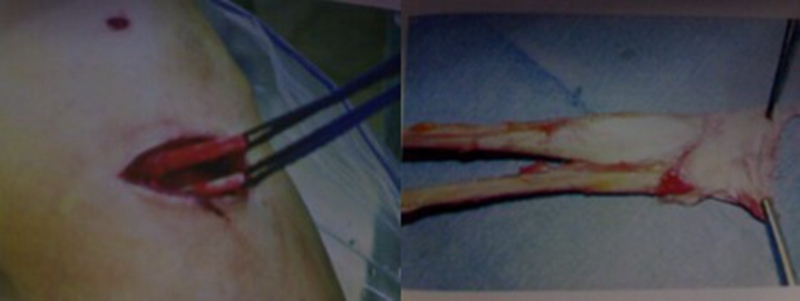

(2)腘绳肌腱:是目前临床最常用的自体移植物。重建后韧带的强度不逊于自体骨髌腱骨,半腱肌腱与股薄肌腱单根并用,初始强度平均可达2736N,大于正常ACL的断裂强度,接近髌腱1/3部的强度,而且局部创伤小,取材方便。

不足之处:关节的某些运动(内旋、屈膝)存在潜在的影响,重建的前交叉韧带需负更大的拉力;取腱失败,则需取其它部位移植物进行手术;切取的肌腱太细,则重建的交叉韧带亦细小,以后发生再断裂的机会增加;康复时间较长。